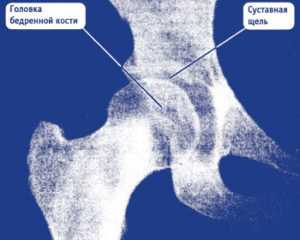

Снимок 2. Пациент обратился к врачу по поводу боли в правом паху и правом бедре, возникающей только при ходьбе или вставании со стула.

Коксартроз 2-й стадии. Фотография из архива доктора Евдокименко

Вот что мы видим на снимке пациента:

- головка бедренной кости «подтянулась» к вертлужной впадине, расстояние между костями совсем небольшое (уменьшение размеров суставной щели). Это говорит о том, что суставной хрящ, покрывающий сочленяющиеся части костей, стал гораздо тоньше (как вы помните, на рентгене сам хрящ не виден);

- оставшись без «хрящевого амортизатора», головка бедренной кости стала деформироваться, частично расплющиваться. Она теперь не такая идеально-круглая, как должна быть.

Такие рентгенологические изменения соответствуют коксартрозу второй стадии.